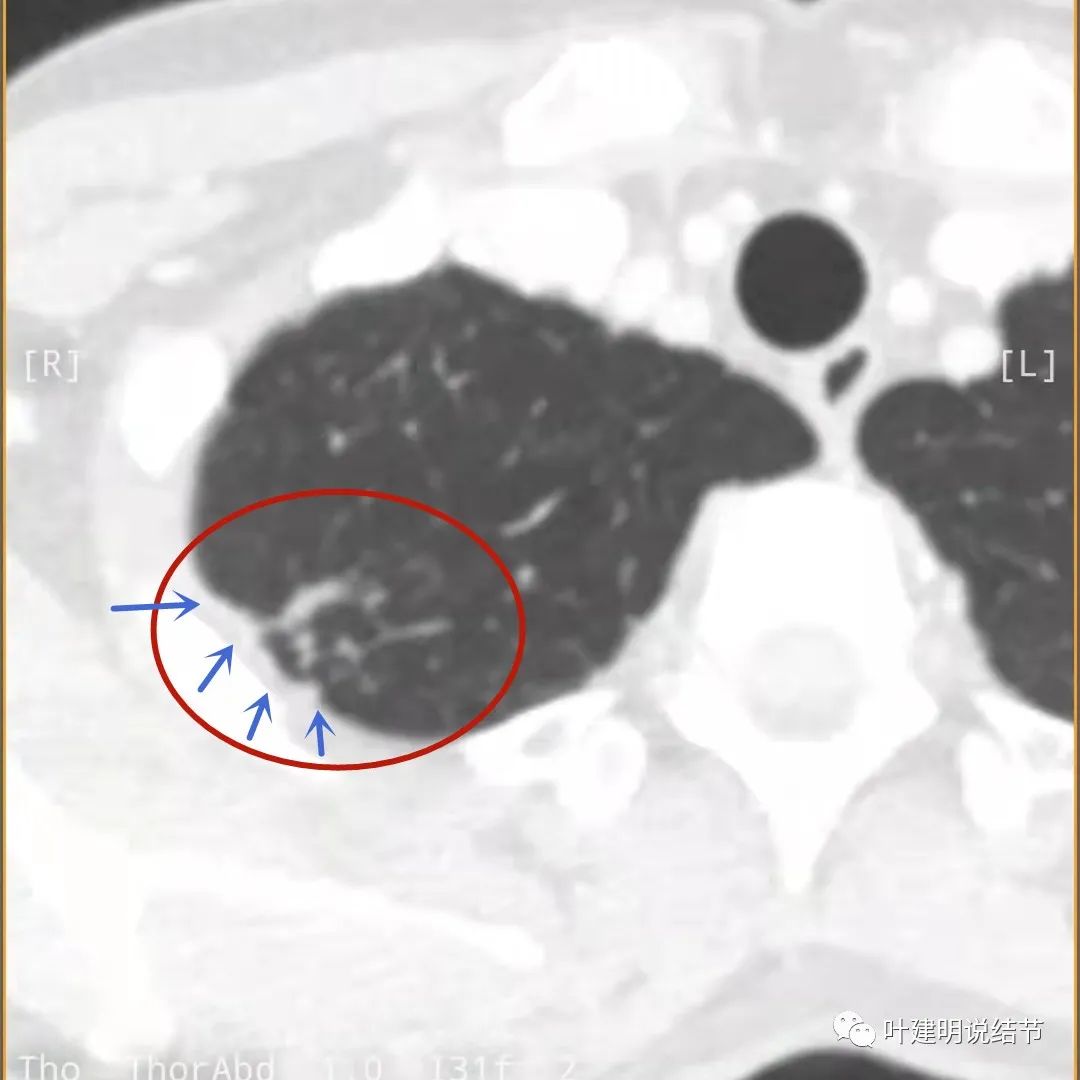

我们再来看薄层的CT图像:

主病灶边界较清(红色箭头),实性部分密度过高(粉色箭头),病灶边缘向内凹,缺乏膨胀性(桔色箭头),病灶有空腔(黄色箭头)

邻近胸膜有增厚(蓝色箭头),主病灶的壁密度过高且整个壁密度都高(粉色箭头),旁边有磨玻璃影,散且模糊(砖色箭头)。内壁不均质(此不舒服)

邻近胸膜有增厚(蓝色箭头),主病灶囊壁密度过高(粉色箭头),内部有突起(细红色箭头),旁边有磨玻璃影,散且模糊(砖色箭头),中间有空腔,内壁有些区域又是光滑的

邻近有卫星灶(绿色箭头),主病灶密度过高(粉色箭头),旁边有磨玻璃影,散且模糊(砖色箭头)

邻近胸膜有增厚(蓝色箭头),主病灶边缘较为平直,缺乏膨胀性(桔色箭头),实性部分密度过高(粉色箭头),旁边有磨玻璃影,散且模糊(砖色箭头)

病灶边缘较为平直,膨胀性不足(桔色箭头)